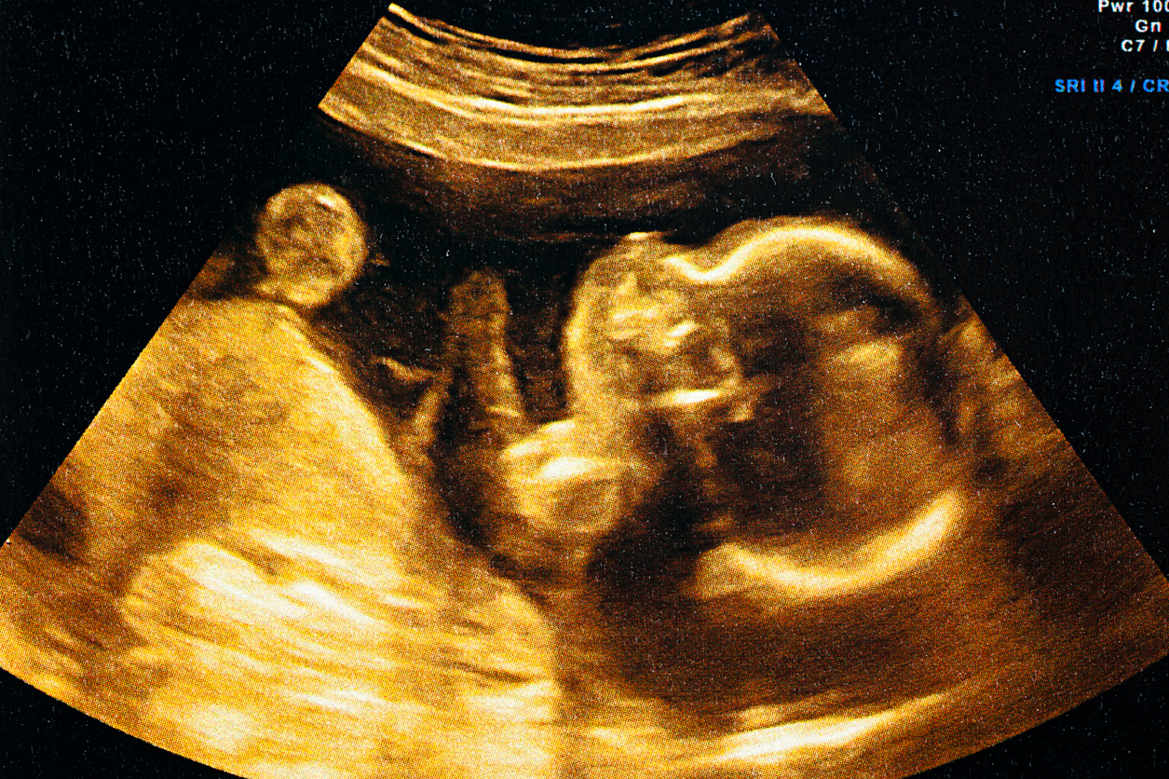

Les premiers instants du cerveau

Huma Khamis s'intéresse aujourd'hui à la naissance du cerveau.

Comment se construit-il? Quels circuits se mettent en place et quand?

Denis Jabaudon, professeur au Département de neurosciences fondamentales à l'Université de Genève (UNIGE), et Joel Fluss, médecin-adjoint agrégé au sein du secteur de neuropédiatrie à l'Hôpital des enfants de Genève, nous parlent des premiers moments de vie du cerveau.